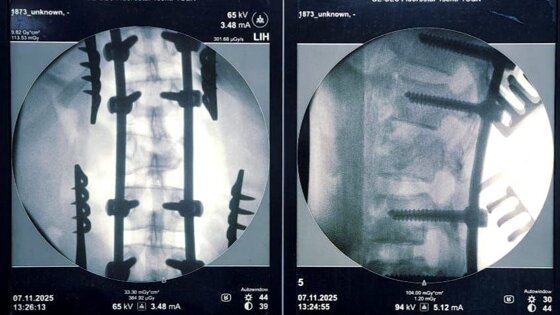

Пациентке диагностирована сочетанная травма: тупая травма грудной клетки, ушиб левого легкого, закрытый неосложненный перелом ребра слева, повреждение позвонков, сдавление спинного мозга с нарушением функций тазовых органов, – сообщил нейрохирург Александр Попов.

Была проведена операция – спинной мозг высвобожден из сдавления, восстановлены конфигурация сломанного позвонка и ось позвоночника, проведена стабилизация позвоночного столба металлоимплантами. Она длилась более двух часов.